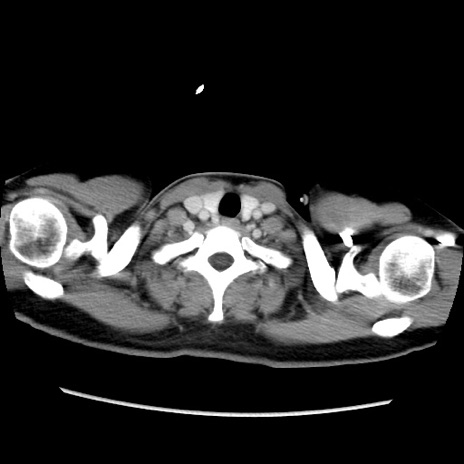

症例39(横断像)

【症例】40歳代女性

【主訴】上下腹部痛

【現病歴】2日目から下腹部痛あり。夜間は痛みで眠れなかった。昨日より上腹部痛と下痢が出現。臥位で痛みは軽快したため、休んでいた。本日になって臥位でも立位でも痛みが強くなってきたため救急要請。

【既往歴】子宮内膜症

【身体所見】部:平坦・軟、左上下腹部に圧痛あり、反跳痛あり。

【データ】WBC 21800、CRP 26.78